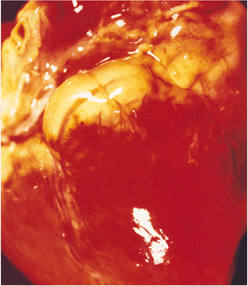

임상증상6

사진56 사진57 사진58

설명56 설명57 설명58